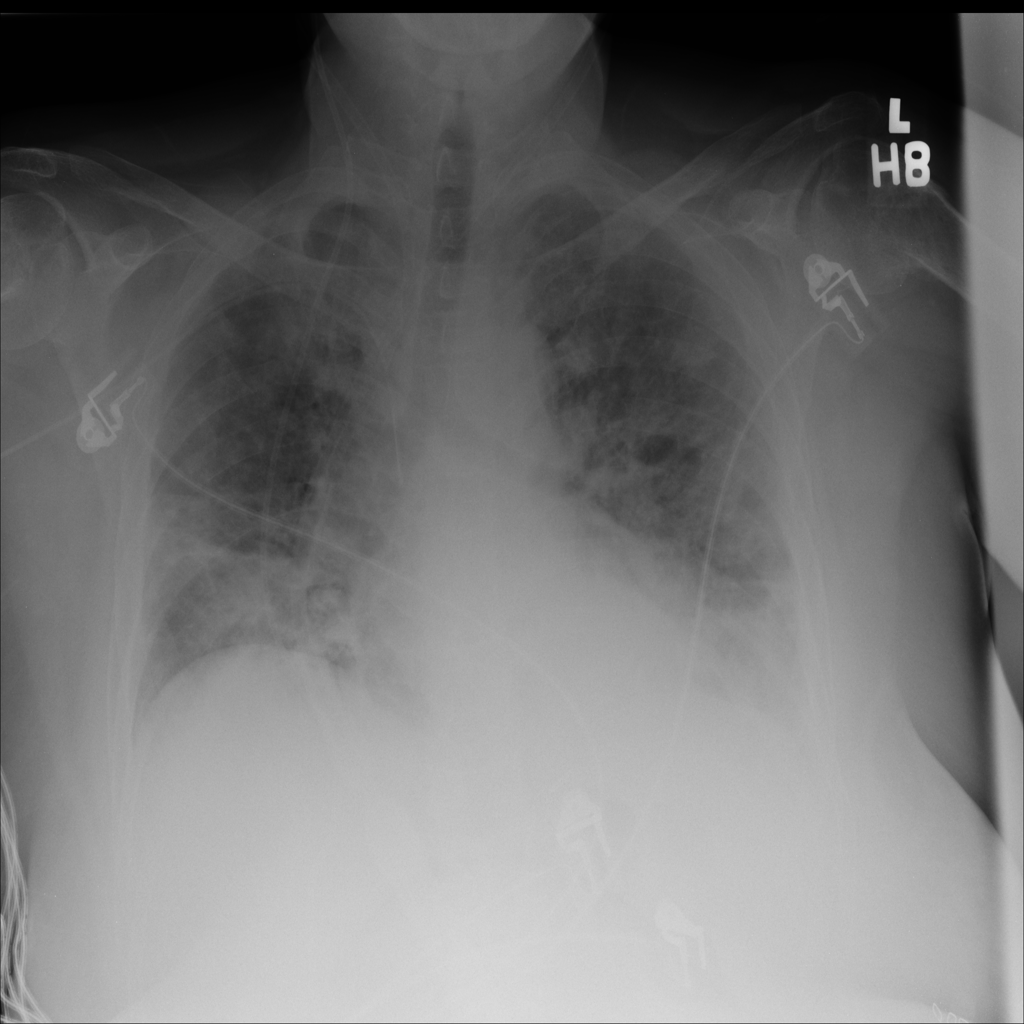

Showing up to 90 reference images for Pneumonia.

PAT-A1E2 · IMG-001Pneumonia

PAT-A1E2 · IMG-001

AP